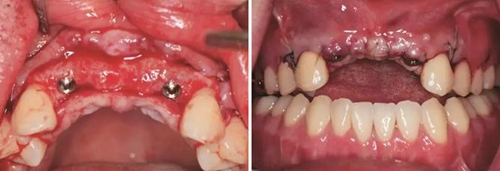

(3)2015年2月:Onlay植骨后6月行種植手術(shù)

術(shù)前再次拍攝CBCT,顯示牙槽嵴寬度較植骨當(dāng)日有一定量的吸收,測(cè)量可用骨寬度,12位點(diǎn)為3.7mm-10.9mm,22位點(diǎn)為5mm-10.9mm。做術(shù)前準(zhǔn)備,用0.12%的復(fù)方氯己定漱口液含漱3次,每次15ml,含漱1min。采用無(wú)痛麻醉機(jī)(STA),復(fù)方鹽酸阿替卡因進(jìn)行口內(nèi)局部浸潤(rùn)麻醉,將麻醉藥物緩慢注入術(shù)區(qū)的牙槽嵴骨膜下方。翻瓣并剝離粘骨膜后充分暴露牙槽骨,取出先前固定骨塊的鈦釘,確認(rèn)植入位點(diǎn),小球鉆定點(diǎn),使用BEGO骨水平種植體及其配套器械(BEGO公司,德國(guó)),根據(jù)擬植入種植體長(zhǎng)度以及直徑大小,逐級(jí)備洞,植入2顆種植體,均為BEGO,RSX植體,直徑為3.75mm,長(zhǎng)度為15mm,獲得35Ncm以上植入扭矩,用種植體穩(wěn)定性測(cè)量?jī)xOsstell ISQ (Osstell公司,瑞典)測(cè)量ISQ值:12、22位點(diǎn)種植體均為79,種植體平臺(tái)位于骨下約1mm,術(shù)后上愈合基臺(tái),嚴(yán)密縫合創(chuàng)口。

圖1 植骨術(shù)前口內(nèi)正面觀 圖2 植骨術(shù)前口內(nèi)頜面觀

圖11 植骨后6月種植術(shù)前 圖12 種植術(shù)前翻瓣后見少量鈦釘螺紋暴露

圖13 取出鈦釘后 圖14 攜帶體示植體位置方向良好

圖15 種植術(shù)后 圖16 種植后嚴(yán)密縫合創(chuàng)口

圖17 CBCT測(cè)量骨量變化 圖18 早期修復(fù)戴牙當(dāng)天